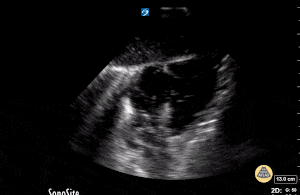

This is a subcostal view during pulse check in a patient presenting in cardiac arrest. The image demonstrates no organized cardiac movement. Small bubbles can be seen in the cardiac chambers which indicates no significant forward flow.